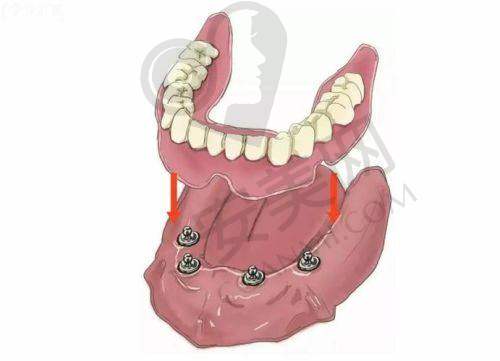

all - on - 4 半口种植牙是一种精良的牙齿种植技术。它通过在牙槽骨内植入四颗种植体,然后利用这四颗种植体来支撑半口牙桥,从而实现半口牙齿的修复。与传统的种植牙技术相比,all - on - 4 半口种植牙具有许多优势。

首先,手术时间短。传统的半口种植牙可能需要植入更多的种植体,手术过程复杂,时间较长。而 all - on - 4 半口种植牙只需要植入四颗种植体,大大缩短了手术时间,减少了患者的痛苦。其次,费用相对较低。由于减少了种植体的使用数量,all - on - 4 半口种植牙的费用相对传统种植牙更为亲民。末尾,稳定性好。四颗种植体呈特定的角度植入牙槽骨内,能够提供足够的支撑力,使牙桥更加稳定,咀嚼功能也能得到良好的修复。